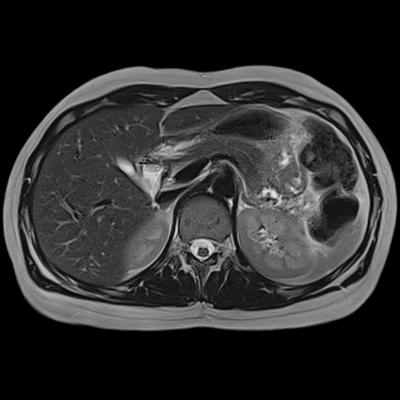

На УЗИ мягких тканей живота можно различить мышцы, подкожный жировой слой, фасции, определить наличие или отсутствие патологических образований. Мышцы обладают меньшей эхогенностью, нежели оболочки, которые их окружают. Грыжи, опухоли и абсцессы выглядят как необычные участки, расположенные между мышечными слоями. Опухоли обычно имеют повышенную эхогенность. Гематомы представляют собой гипоэхогенные образования, имеющие неоднородную структуру. Абсцессы - это скопления жидкости с переменной эхогенностью.

Результат МР-сканирования мягких тканей шеи